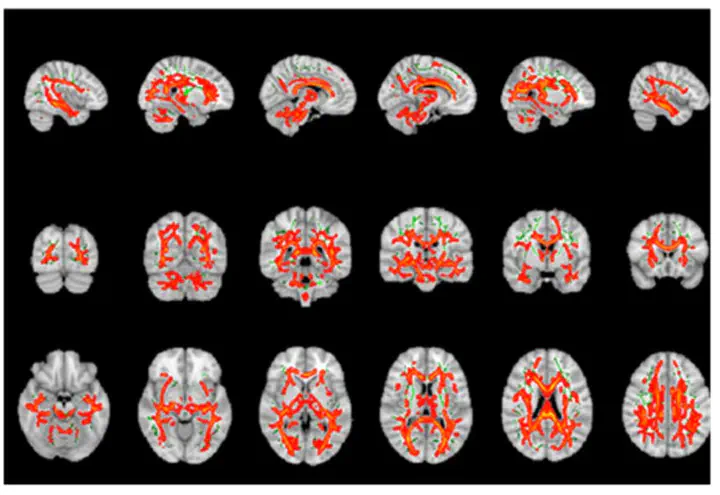

Advanced structural brain imaging techniques, such as diffusion tensor imaging (DTI), have been used to study the relationship between DTI-parameters and cognitive scores in multiple sclerosis (MS). In this study, we assessed cognitive function in 61 individuals with MS and a control group of 35 healthy individuals with the Symbol Digit Modalities Test, the California Verbal Learning Test-II, the Brief Visuospatial Memory Test-Revised, the Controlled Oral Word Association Test, and Stroop-test. We also acquired diffusion-weighted images (b = 1000; 32 directions), which were processed to obtain the following DTI scalars: fractional anisotropy, mean, axial, and radial diffusivity. The relation between DTI scalars and cognitive parameters was assessed through permutations. Although fractional anisotropy and axial diffusivity did not correlate with any of the cognitive tests, mean and radial diffusivity were negatively correlated with all of these tests. However, this effect was not specific to any specific white matter tract or cognitive test and demonstrated a general effect with only low to moderate individual voxel-based correlations of textless0.6. Similarly, lesion and white matter volume show a general effect with medium to high voxel-based correlations of 0.5-0.8. In conclusion, radial diffusivity is strongly related to cognitive impairment in MS. However, the strong associations of radial diffusivity with both cognition and whole brain lesion volume suggest that it is a surrogate marker for general decline in MS, rather than a marker for specific cognitive functions.